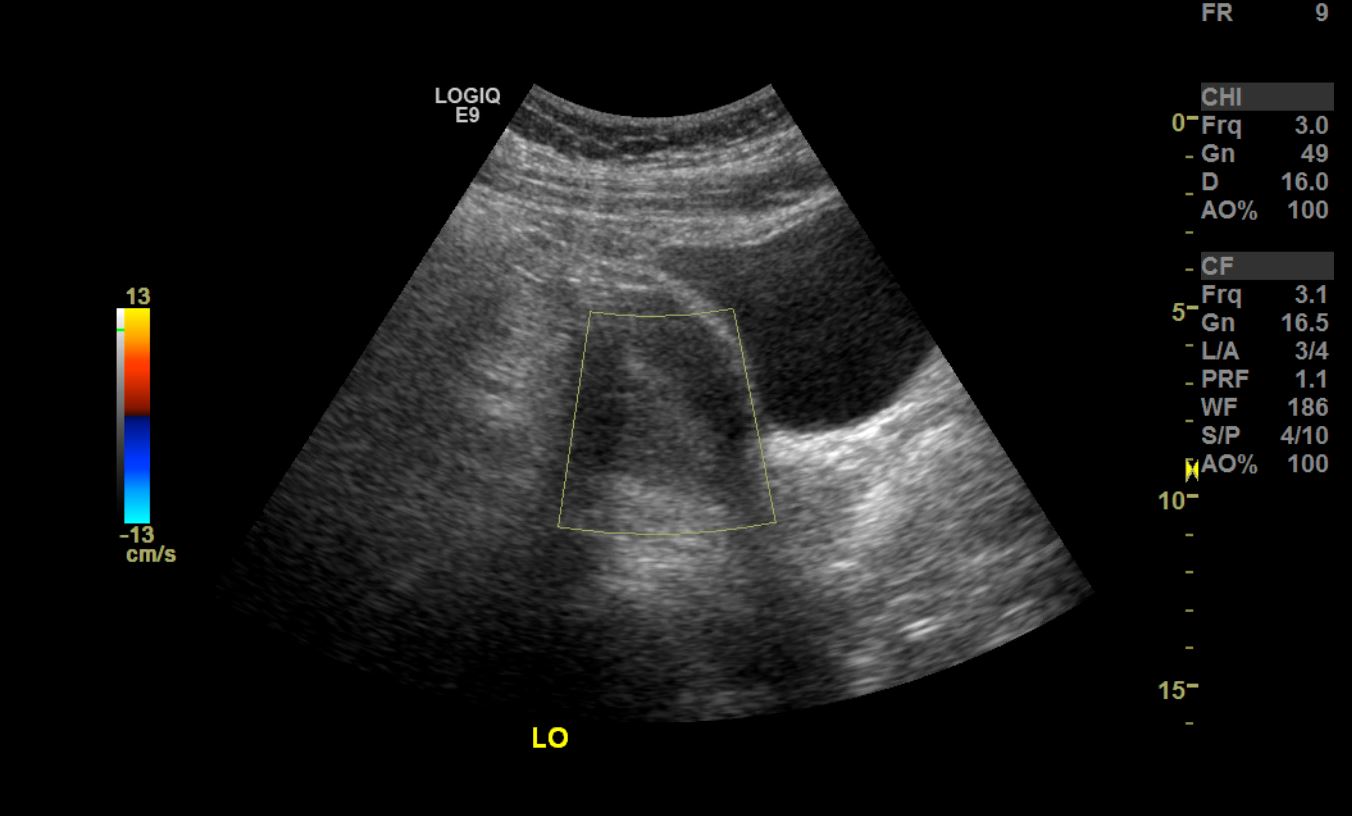

From www.researchgate.net

] Ultrasound image showing thickened endometrium Download Scientific Thickened Endometrium Obesity Reversible risk factors such as obesity and the use of hormone replacement therapy (hrt) should be p identified and addressed if possible. Endometrial cancer (ec) is the most common gynaecological malignancy in developed countries, and its incidence is increasing in. Obesity has been found to increase endometrial thickness independently. Hypertension may increase the endometrial. Further investigations should be made on. Thickened Endometrium Obesity.